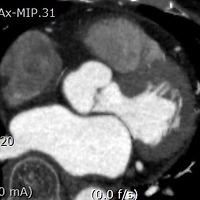

GLP-1 receptor agonist와 DPP4 inhibitor의 비교 및 GLP-1R agonist의 승인 현황

GLP-1R agonist는 insulin 분비 증강을 유발하고, 포만감 증진과 장관 내 소화 시간 지연을 유발하여 살을 빼 주는 효과도 동반됩니다. 저혈당 유발의 위험이 다른 약에 비해 적은 등 많은 장점이 있으나, insulin처럼 주사용제로밖에 사용을 할 수가 없어서 long acting (weekly) 제제의 개발이 많이 이루어지고 있었습니다. 지난 9월 27일, Eli Lilly가 GLP-1R agonist 경구제형을 개발하는 회사와 협업을 발표했습니다.